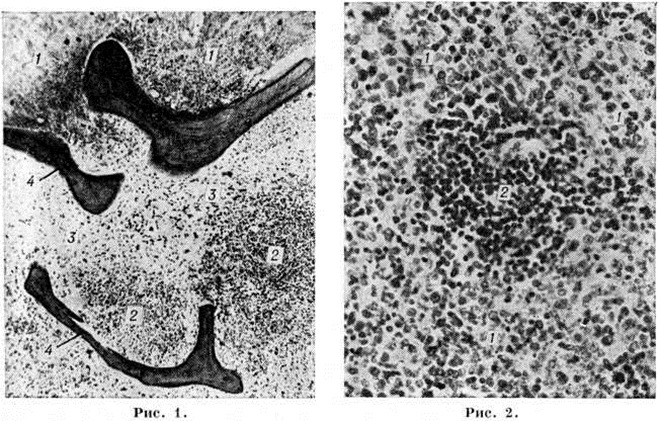

Рис. 1. Микропрепарат костного мозга при остром лимфобластном лейкозе: очаговый коагуляционный некроз ткани (1) на фоне лейкозной инфильтрации (2), в окружности некроза кровоизлияния, скопления макрофагов (3), рассасывание костной ткани с истончением костных балок (4). Окраска гематоксилин-эозином; × 80.

Рис. 2. Микропрепарат ткани селезёнки при остром монобластном лейкозе: видна лейкозная инфильтрация (1), резкое уменьшение размеров фолликула (2). Окраска гематоксилин-эозином; × 280.

В костном мозге, по данным трепанобиопсии, на первых стадиях заболевания скопления бластных клеток являются очаговыми, в достаточном количестве обнаруживаются элементы деятельного костного мозга. Нередко наблюдаются острые расстройства кровообращения, участки гипоплазии, могут обнаруживаться некрозы. Прогрессирование заболевания характеризуется увеличением числа и размеров лейкозных разрастаний, их слиянием, а затем диффузной инфильтрацией ткани костного мозга. Количество нормальных кроветворных клеток заметно уменьшается. Часто имеется инфильтрация надкостницы, возможно распространение процесса в окружающие мягкие ткани. Развитие лейкозных разрастаний сопровождается выраженным рассасыванием костной ткани, преимущественно по типу гладкой резорбции. Очень редко в этом процессе принимают участие остеокласты. Вследствие частичного, а местами и полного рассасывания костных балок происходит значительное расширение костномозговых полостей, истончение, а в некоторых участках разрушение кортикального слоя. В раннем детском возрасте резкие изменения наблюдаются в зоне энхондрального окостенения. При острых Лейкозы редко отмечается очаговое новообразование атипичной костной ткани, богатой остеоидом, разрастание фиброзной ткани. Наряду с мелкими фокусами некроза иногда возникают обширные инфарктообразные коагуляционные некрозы, определяемые макроскопически в виде жёлто-белых сухих участков; в окружности наблюдаются кровоизлияния, возможно скопление макрофагов (рисунок 1). В области лейкозных разрастаний нередко обнаруживается истончение и частичный распад ретикулярных волокон. Описаны наблюдения с очаговым или диффузным миелофиброзом, который чаще выявляется при миелобластном Лейкозы. В таких случаях при пункции обычно не удаётся получить костный мозг и для установления диагноза необходимо исследование материала трепанобиопсии.

Лейкозная инфильтрация ткани селезёнки и лимфатических, узлов сопровождается уменьшением размеров (рисунок 2) и числа фолликулов вплоть до полного их исчезновения. В селезёнке часто наблюдается инфильтрация трабекул с разволокнением стенок трабекулярных сосудов, с деформацией и сужением их просвета, имеются поля кровоизлияний. В лимфатических, узлах вначале возникают очаговые инфильтраты, которые по мере прогрессирования болезни увеличиваются в размерах, и поражение становится диффузным.